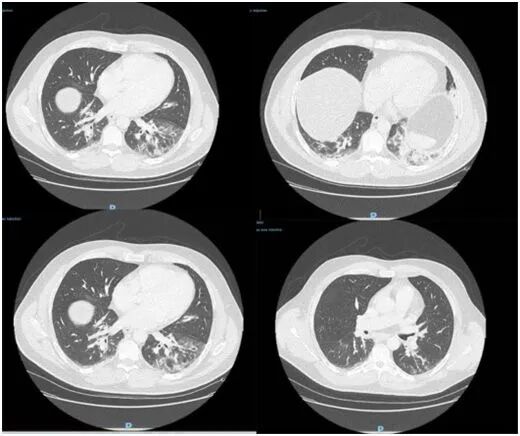

初步检查无异常,所做CT扫描显示双侧下叶磨玻璃样阴影(图3),入院时他有淋巴细胞减少症,C反应蛋白和纤维蛋白原升高,但原降钙素处于正常范围。在急诊病房采集的痰液样本中没有发现病原体。这名患者入住ICU,接受抗生素治疗,因病情发生好转于2019年12月29日出院。

图3.在基线时进行胸部CT扫描。